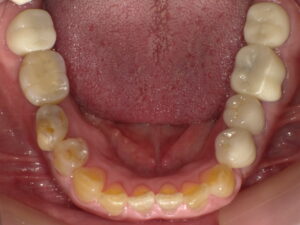

この2つの写真を見比べて、どちらのお口の中の印象が良く見えますか?(比較写真2枚)

術後

見比べてみると、白い歯の方がきれいに見えますよね。

この患者さまはお口を開けた時に銀歯が目立つということで、順番に白い被せ物に変えていきました。

治療が終わると「お口の中が明るくなったし、銀歯をきにしなくていいので自信を持って話せます。

また上の歯もやっていきたいなぁ」とおっしゃってみえました。

お口の中が金属フリーのなると、見た目の印象が明るくなるのはもちろん、

金属アレルギーの問題もクリアできると思います。